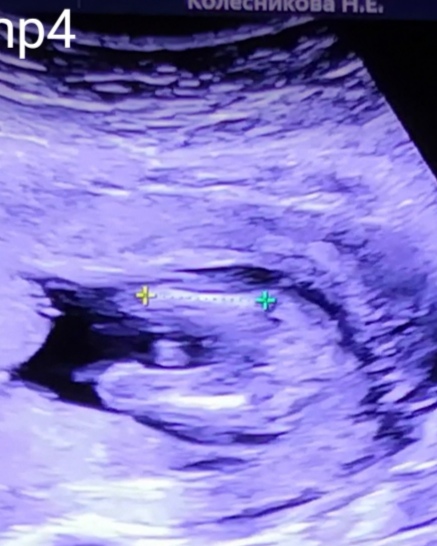

Мне все не успокоится😉 Изучаю видео, делаю скрины с последнего узи. И вот нашла замечательный ракурс, где измеряли бедренную кость. Увеличила, и я увидела, то, что обещали мне и то, что я очень хочу видеть🤗😂 Девочки, а что видете вы на этом обрезанном и приближенном фото?

Мошонка тут, мне кажется. У меня есть фото пирожка дочи, он совсем не такой.

Нет, это верх на фото. Сверху бедро измеряли, внизу ступни, видишь? Вот полное:

Ну сверху то пирожок вообще не видно должно быть. А вообще я не знаток УЗИ 😆 Раз вам сказали девочка, значит так и есть)))

Не могу прикрепить фото( но очень похоже на наше и у нас это были всё таки бубенчики))